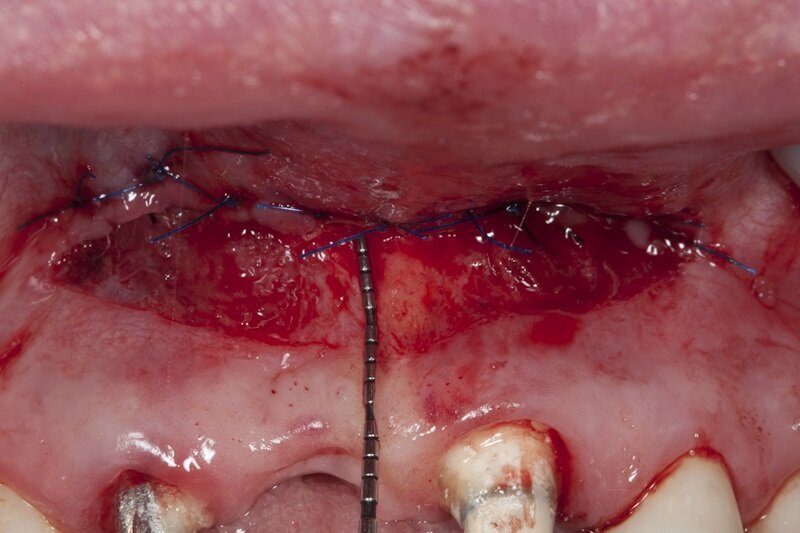

Na podstawie uzyskanych danych zasugerowano pacjentce etapowe rozwiązanie zaistniałej sytuacji, na co uzyskano zgodę. Pierwszy etap obejmował frenulotomię i westibiloplastykę w celu uzyskania poprawy zastanych warunków pod względem tkanek miękkich. Zaplanowano dowierzchołkowe przesunięcie płata śluzówkowego z pozostawieniem okostnej. Zabieg przecięcia błony śluzowej przeprowadzono przy użyciu lasera Er:YAG przy następujących ustawieniach: VLP 120 mJ, 20 Hz, a następnie przesunięty dowierzchołkowo płat błony śluzowej wraz z przyczepami mięśni przyszyto szwami materacowymi Prolene 5.0 do okostnej (Ryc. 4). Następnie, przy użyciu głowicy Genova i lasera Nd:YAG o parametrach: MSP, 0,5 W, 20 Hz dokonano naświetlenia rany w 4 miejscach po 60 s na punkt (Ryc. 5-7).

Ryc. 5_Zabieg westibuloplastyki.

Ryc. 7_Zabieg biomodulacji w 4 punktach.